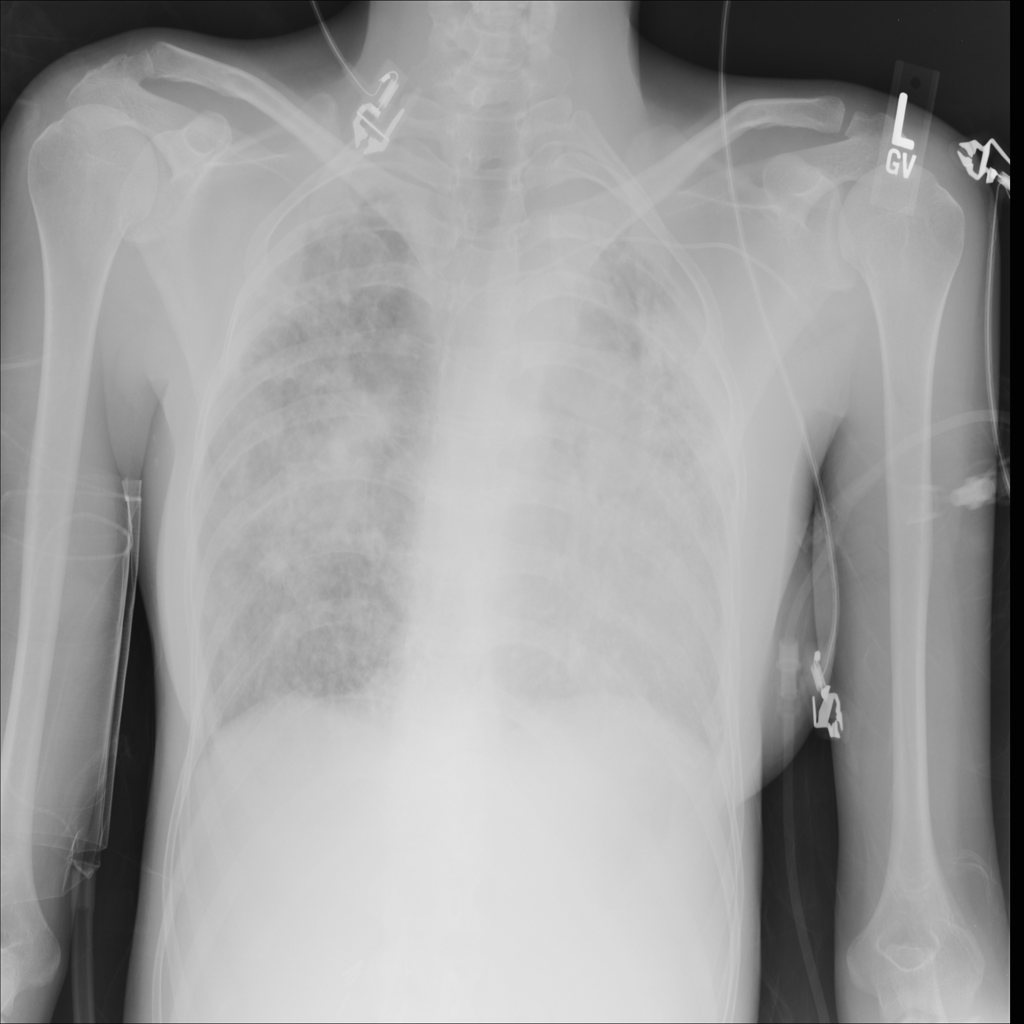

Consolidation

Consolidation refers to air-space filling that makes part of the lung appear denser on imaging.

Showing up to 90 reference images for Consolidation.

PAT-531A · IMG-006Consolidation

PAT-531A · IMG-006

PA